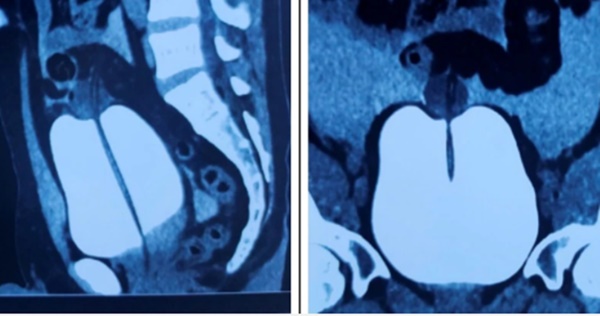

Hình ảnh chụp CT của bệnh nhân T